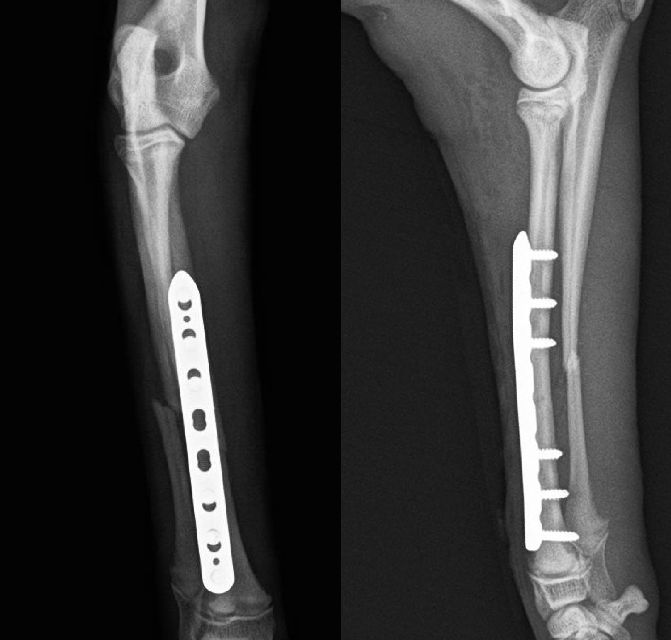

骨折

小型犬の前肢骨折(橈尺骨骨折)は転倒や落下で簡単に骨折します。

ほとんどがプレートとスクリュー固定にて完治できますからできるだけ早期に手術を行います。

術後は関節の拘縮や筋肉の萎縮を予防するため適度な運動とリハビリが重要です。

骨折した肢を負重することで早期に骨癒合が促されます。

骨癒合が得られればスクリューを外す手術を行います。

後肢の骨折(骨盤、大腿骨、脛骨)は高エネルギー外傷(交通事故、高い所からの落下など)で全身にダメージを受けている場合があります。

必ず全身状態の評価を行ったうえで整復固定手術を行います。

【術前】橈尺骨遠位端プレート整復固定 -

【術後】橈尺骨遠位端プレート整復固